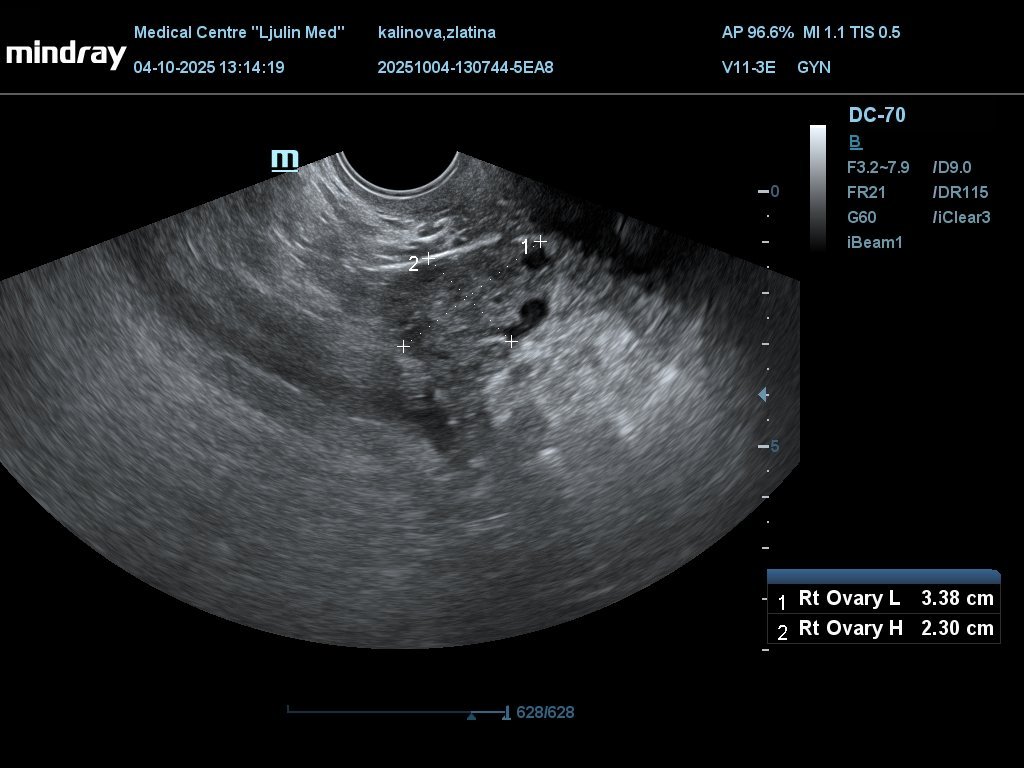

Моля да ми разчетете снимките. Има ли бременност

Последна редакция: сб, 04 окт 2025, 14:11 от Moderator1

Изображенията показват яйчници с антрални фоликули и матка с дебелина на лигавицата 7.6 мм. Във фоликуларна фаза си, демек предстои овулация.

Няма бременност със сигурност.